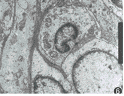

图6 瘤细胞膜外侧有一层清晰的基板,胞浆内细胞器简单,核仁明显,未见桥粒和缝隙连接 EM×1 000

2.病理诊断: 颅内血管外膜细胞瘤多为单发,大体标本肿瘤呈分叶状,表面有丛状血管,瘤内可见大小不等血管腔或血窦,常伴有出血、灶性坏死或囊变。光镜下肿瘤细胞围绕毛细血管壁高度增生,呈旋涡状或放射状排列,细胞大小一致,多角形,胞浆中等,胞质淡染呈空泡状,胞核圆形或卵圆形,核膜明显,染色质多,可见核分裂相,细胞界限不清,细胞间有丰富网状纤维;瘤内血管丰富,毛细血管管径大多小于25 μm,血管壁菲薄,甚至由单层扁平血管内皮细胞构成血管腔,有的可扩张成血窦,相互吻合似“鹿茸”状(图4,5)。通常,分化好者瘤细胞间网状纤维丰富,间变者瘤细胞多,核分裂活跃,坏死、出血及囊变多见,但二者间无明确的组织分界。有时普通病理染色难以与脑膜瘤鉴别,电镜检查和免疫组织化学才可作出诊断。电镜下可见瘤细胞膜外侧有一层清晰的基板,胞浆内细胞器简单,核仁明显,但细胞间无桥粒和缝隙连接,这不同于脑膜瘤(图6)。